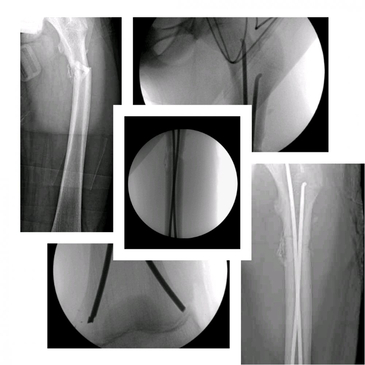

Dr. Rodrigo Aguirre Rojas is the best Orthopedic Surgeon in San Jose del Cabo, Mexico. Book your consultation for Hip and Knee Replacements in Los Cabos, Mexico at PlacidWay. Emergencies like Fractures and Dislocations are also evaluated and treated